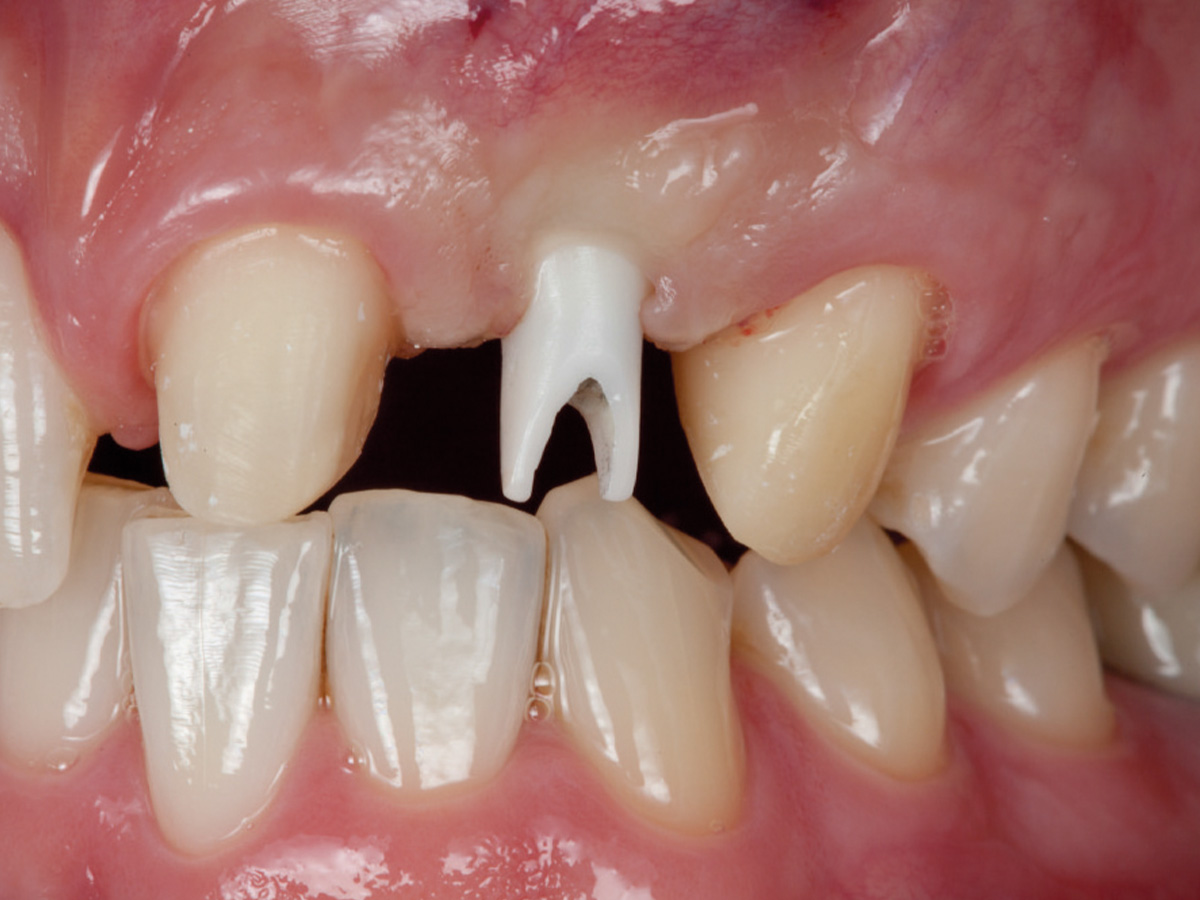

Abbildung 11

Ein Implantat mit 3,8 mm (Ø) konnte in seiner korrekten dreidimensionalen Position eingebracht werden.

Abbildung 12

Regenerierter Alveolarkamm vor der prothetischen Versorgung.

Zu diesem Zeitpunkt kann klinisch und röntgenologisch ein deutlicher Zugewinn von Volumen verzeichnet werden, so dass ein Implantat vom Durchmesser 3,8 mm in der korrekten dreidimensionalen Position eingesetzt werden kann. Mit den beschriebenen augmentativen Maßnahmen konnte ein ästhetisch ansprechendes Gesamtergebnis realisiert werden.